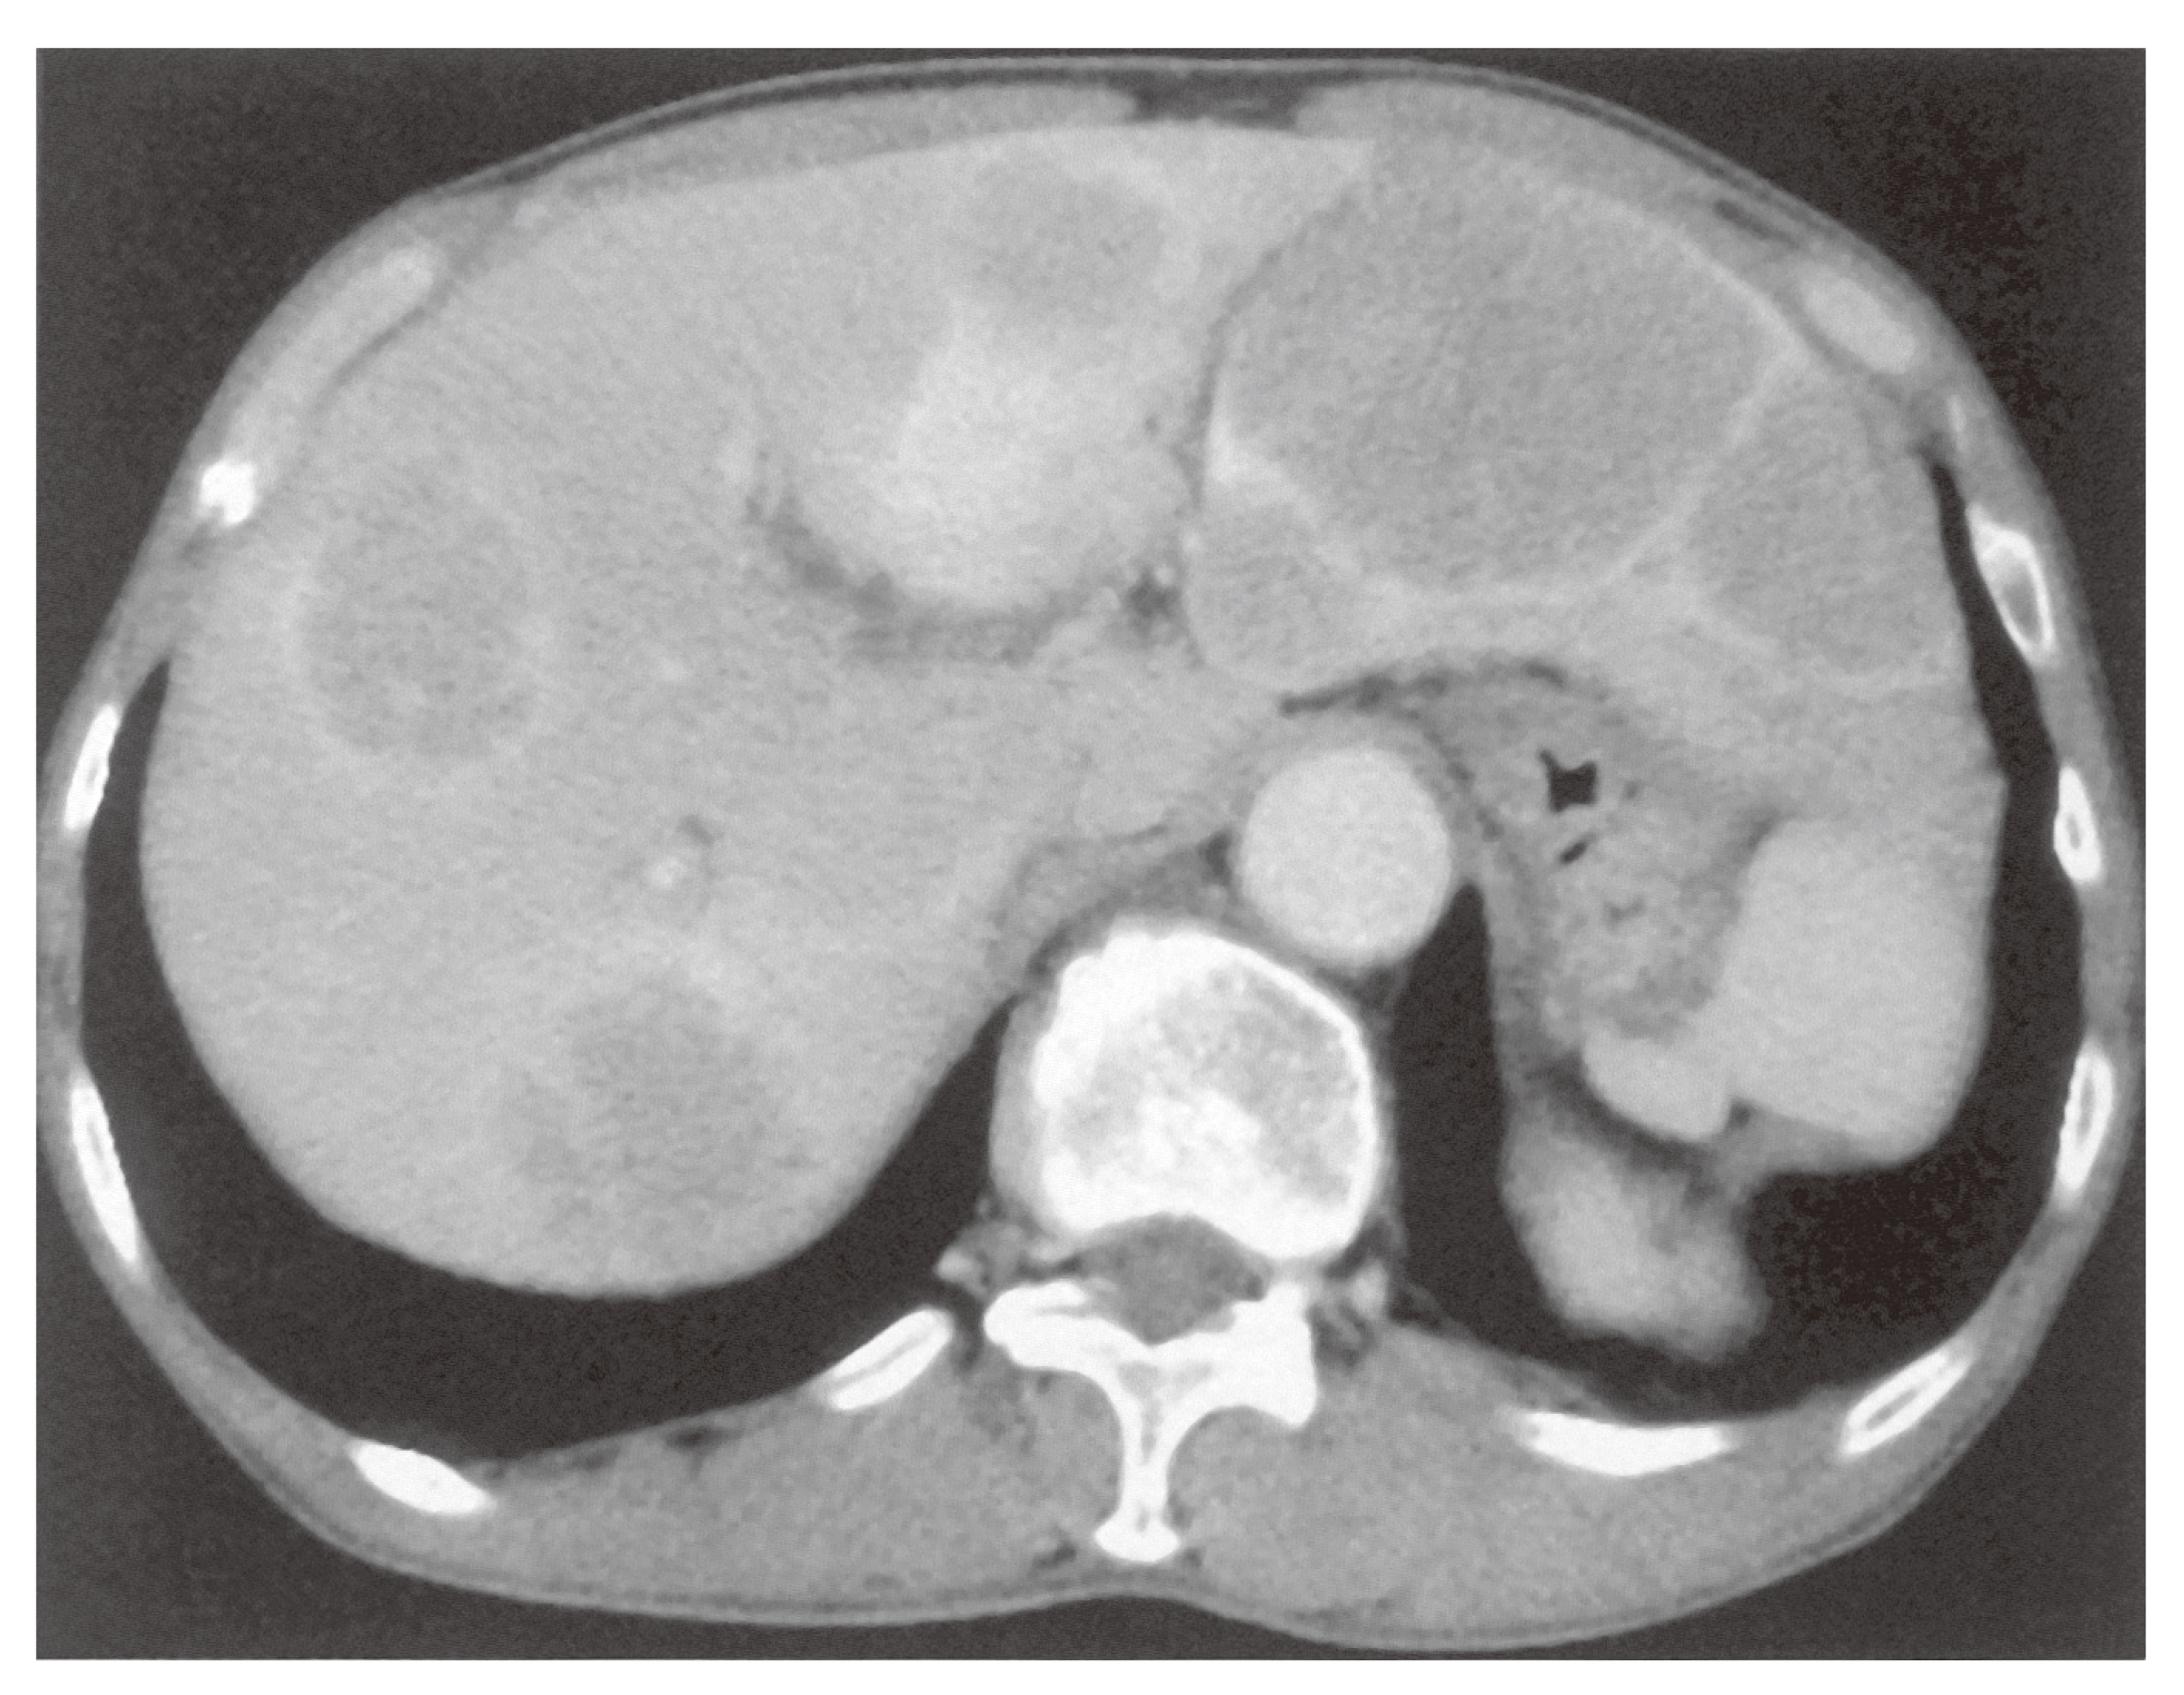

日本がん対策図鑑 | 【標準治療】大腸がん。日本がん対策図鑑 | 【標準治療】大腸がん。100F33 | 大腸癌, 転移性肝癌 国試 | テコプラ。S*i様 白酒 茅台酒 君作 53% 500ml。マーカー、断裁なし。上に押し印ありますので、消して発送します。目立った汚れはありませんが、あくまで中古品なのでご理解ある方ご購入お願いします。。腎盂・尿管・膀胱癌取扱い規約 第2版 – 医学図書出版。。【ピー】レジデントのための糖尿病・代謝・内分泌内科ポケットブック